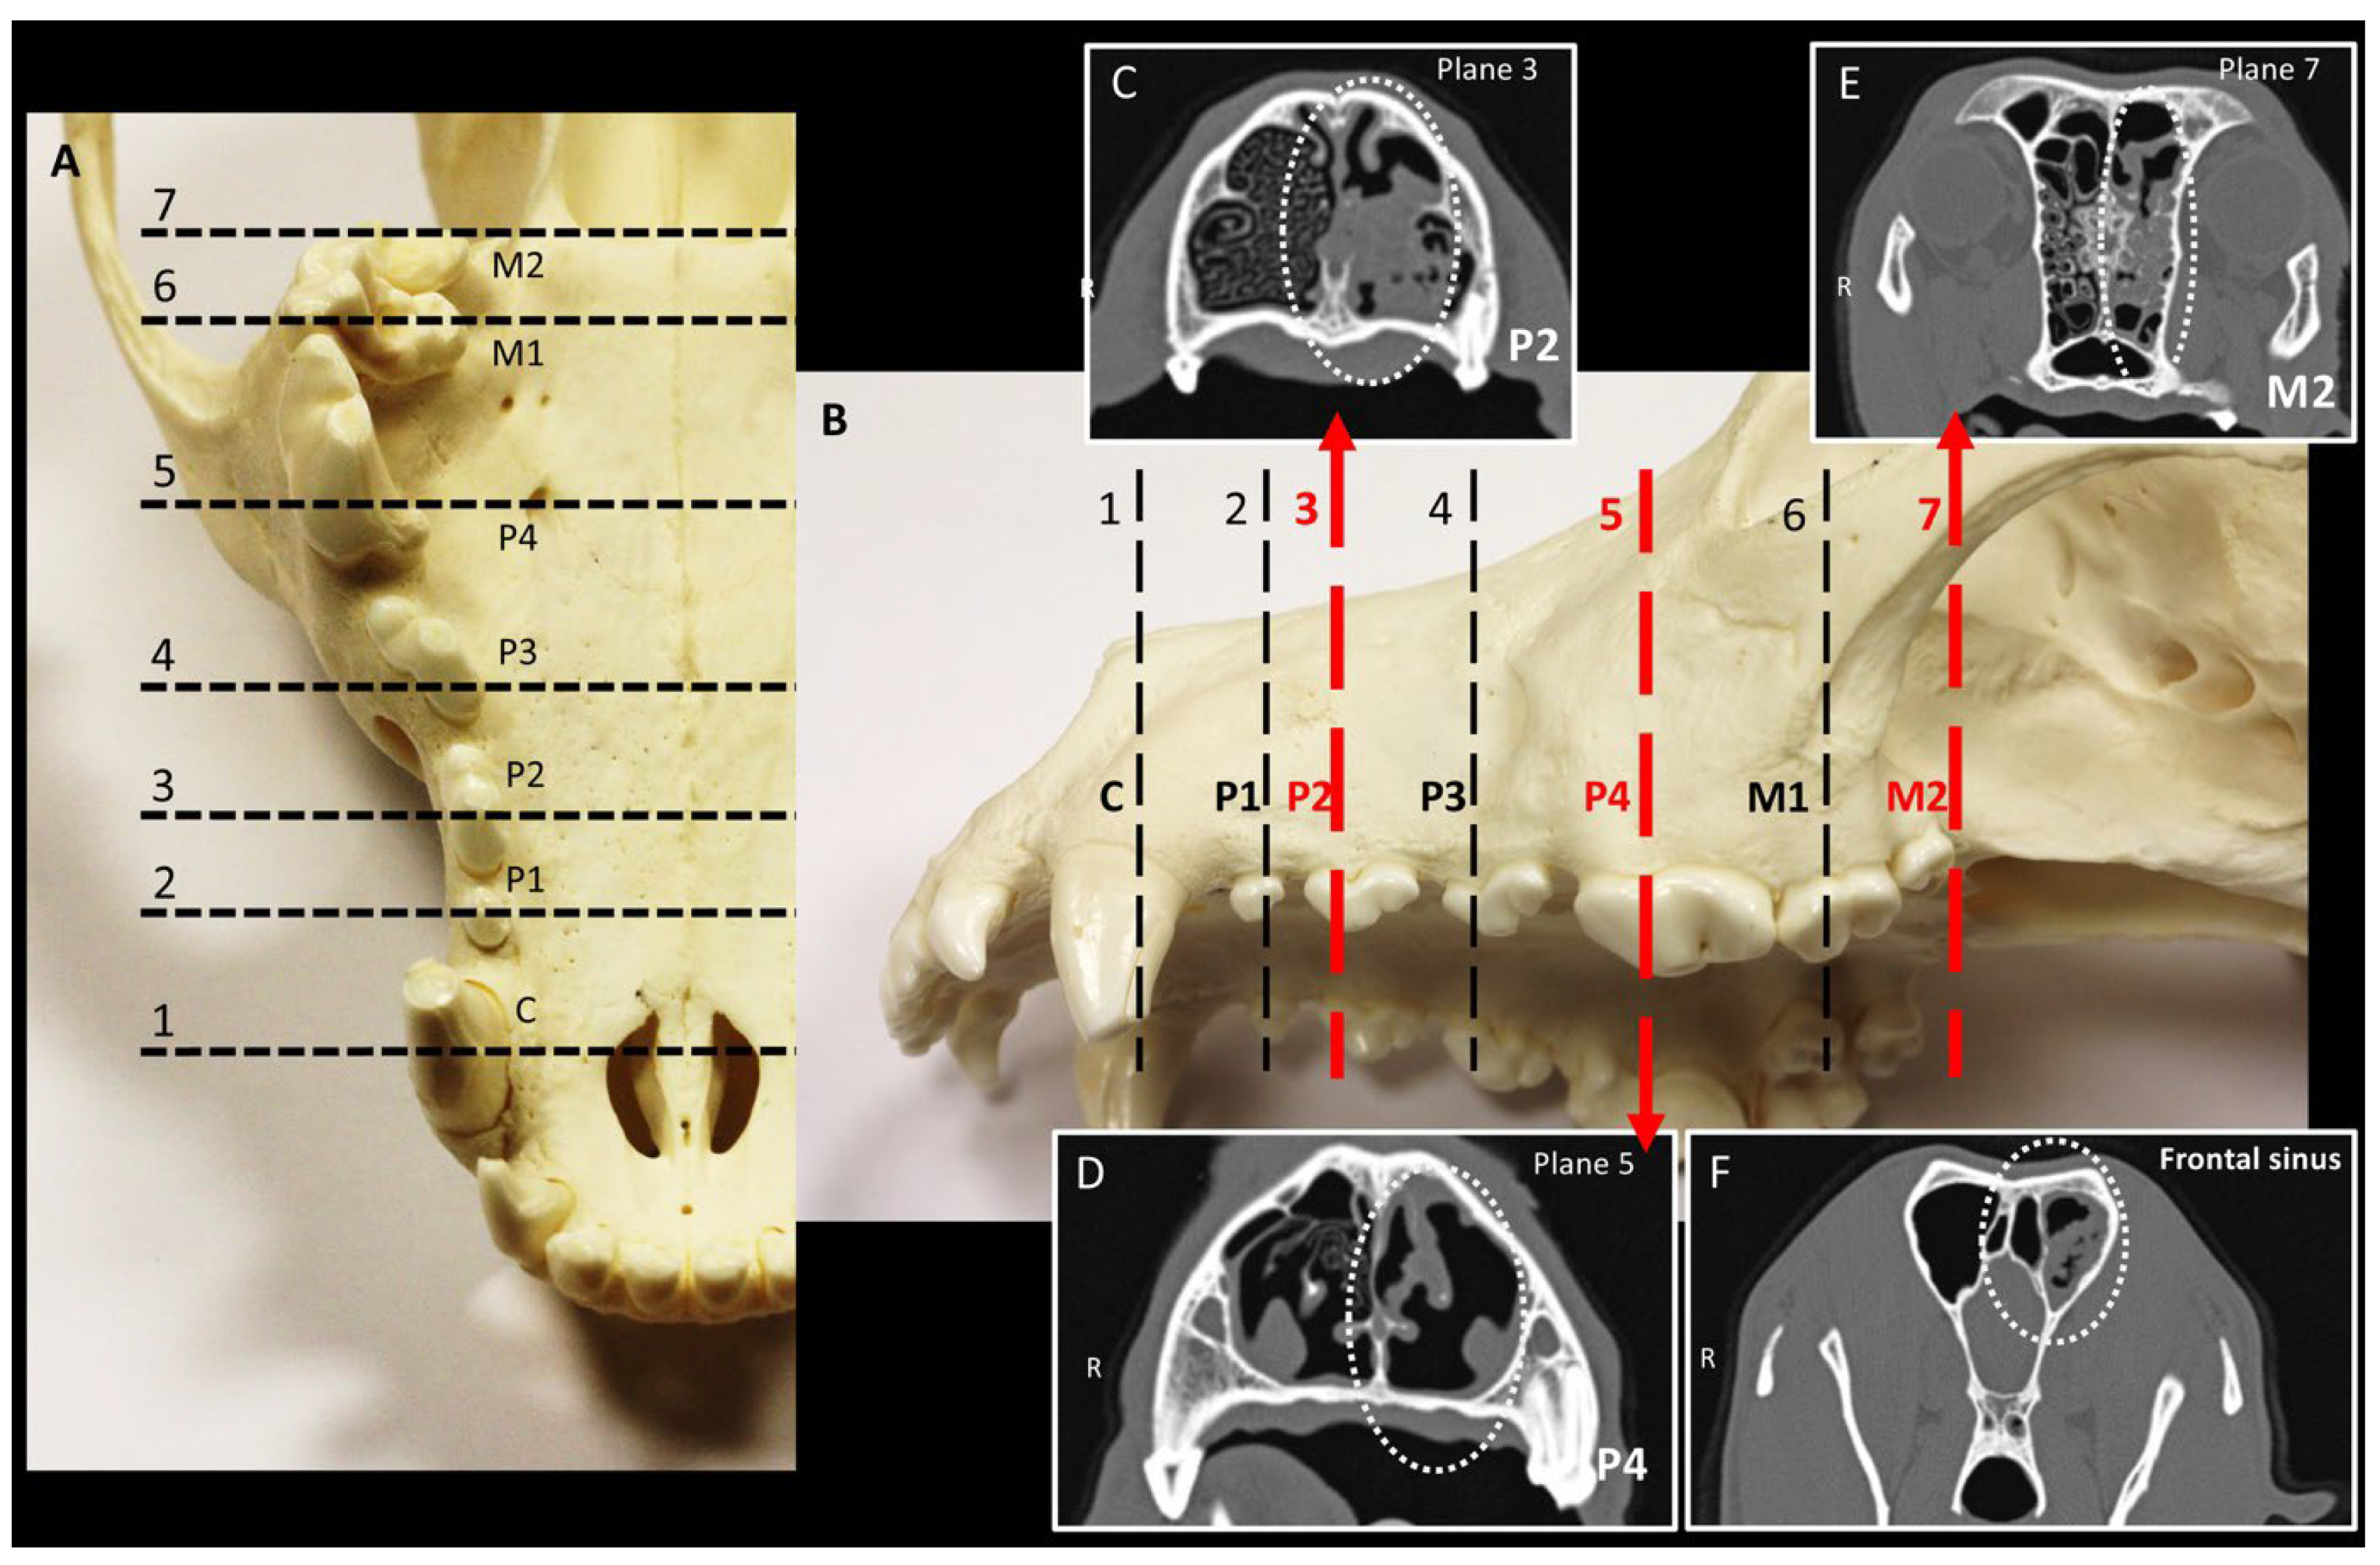

Dogs were positioned in the sternal recumbent position with the hard palate fixed parallel to the scanning table. Transverse image series (1.0 mm) were acquired and used for reformation to obtain sagittal and dorsal views. During CT follow-up studies, efforts were made to ensure comparable positioning of the dog in all examinations, data were analyzed in the same way, and the time between follow-up examinations was documented. For comparison of sectional planes on CT at initial and follow-up scans, the changed nasal cavity areas were determined based on the maxillary teeth in the transverse section. The image series was adapted to a ww/wl 3000/300 for this purpose. In each case, the tooth at the longitudinal center of the transverse section was selected as the reference point (largest size of the pulp cavity; see Figure 1). For the two-rooted maxillary second premolar (P2; Triadan 106/206) and maxillary third premolar (P3; Triadan 107/207), the rostral root was used as the reference point. For the three-rooted maxillary fourth premolar (P4; Triadan 108/208) and maxillary first molar (M1; Triadan 109/209), the rostral lingual and medial roots were considered, as both roots lay in the same sectional plane when properly aligned. For the maxillary secondary molar (M2; Triadan 110/210), the caudal border of the tooth was used as the reference. The frontal sinuses were evaluated at the level of the caudal end of the sphenoid sinus (see Figure 1).

Figure 1. Landmarks for comparative evaluation of sinonasal computed tomography (CT) findings. (A,B) The skull of a dog; section planes 1 to 7 are oriented to the teeth of the maxillary jaw. (CF) Transverse CT images from a dog with primary sinonasal aspergillosis in the left nasal cavity with sinus involvement, (C) at the level of the maxillary second premolar (P2; Triadan 106/206), (D) maxillary fourth premolar (P4; Triadan 108/208), and (E) maxillary second molar (M2; Triadan 110/210), respectively. (F) Sectional plane at the level of the caudal end of the sphenoid sinus.